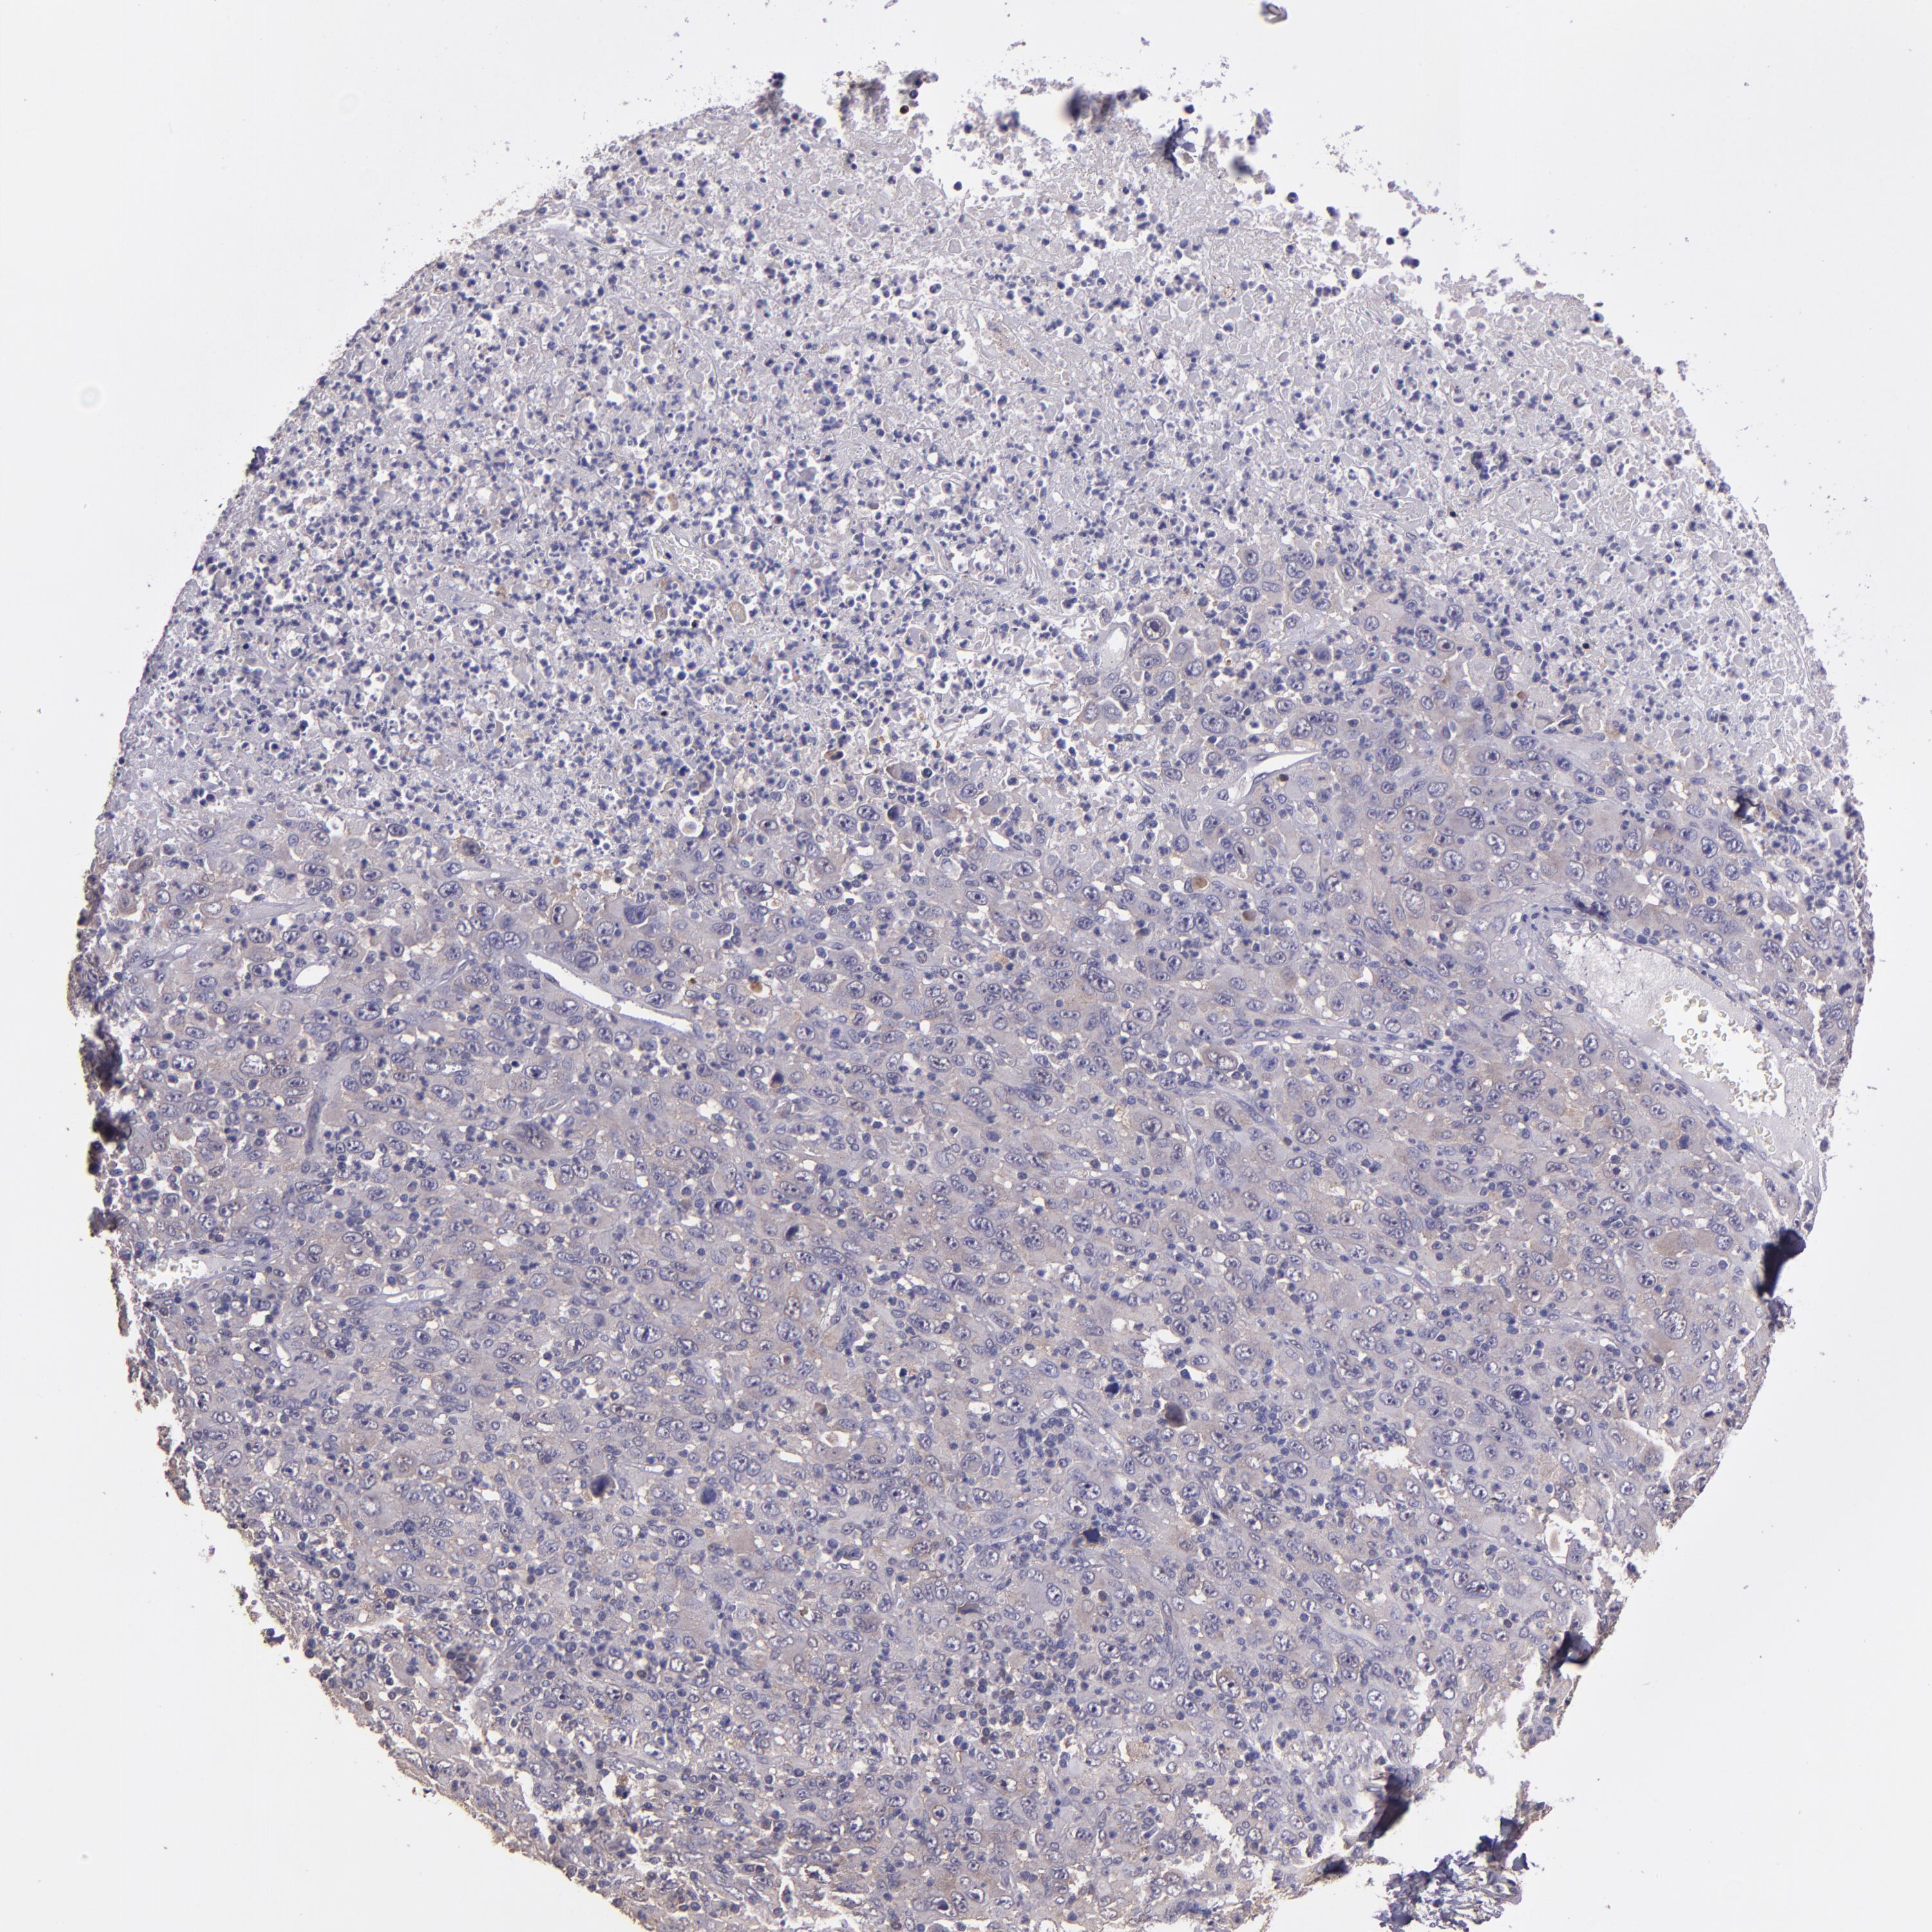

MELANOMA - Protein expressioni

A mouse-over function shows sample information and annotation data. Click on an image to view it in a full screen mode. Samples can be filtered based on level of antibody staining by selecting one or several of the following categories: high, medium, low and not detected. The assay and annotation is described here.

Note that samples used for immunohistochemistry by the Human Protein Atlas do not correspond to samples in the TCGA dataset.

Antibody stainingi

Antibody staining in the annotated cell types in the current human tissue is reported as not detected, low, medium, or high, based on conventional immunohistochemistry profiling in selected tissues. This score is based on the combination of the staining intensity and fraction of stained cells.

Each image is clickable and will lead to virtual microscopy that enables deeper exploration of all samples and also displays staining intensity scores, fraction scores and subcellular localization as well as patient and tissue information for each sample.

Antibody HPA001667

Antibody CAB016724

Malignant melanoma, NOS

Malignant melanoma, Metastatic site